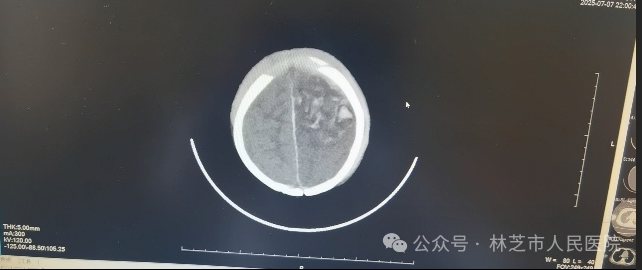

7月7日晚9时,还处于高原适应期的张春敏主任接到儿科值班医生的紧急电话:一名昏迷不醒、呼吸微弱的幼儿被送入医院,双侧瞳孔不等大,生命危在旦夕。尚未克服高原反应的张春敏主任立即电话中指导抢救,顶着高原缺氧的状态急速奔赴医院。查体发现患儿左侧枕部淤肿,凭借丰富经验,他迅速判断患儿存在严重颅脑创伤、颅内出血合并脑疝,当即汇报医院医务科启动绿色通道,连夜联系影像科,并同值班医生护送患儿完成急诊头颅CT检查,确诊为“左侧额颞顶叶脑挫伤、蛛网膜下腔出血、硬膜下/外出血、脑疝”。时间就是生命,张主任立即联系了同批援藏专家神经外科谢韬主任到场评估手术救治。

7月7日晚急诊头颅CT情况